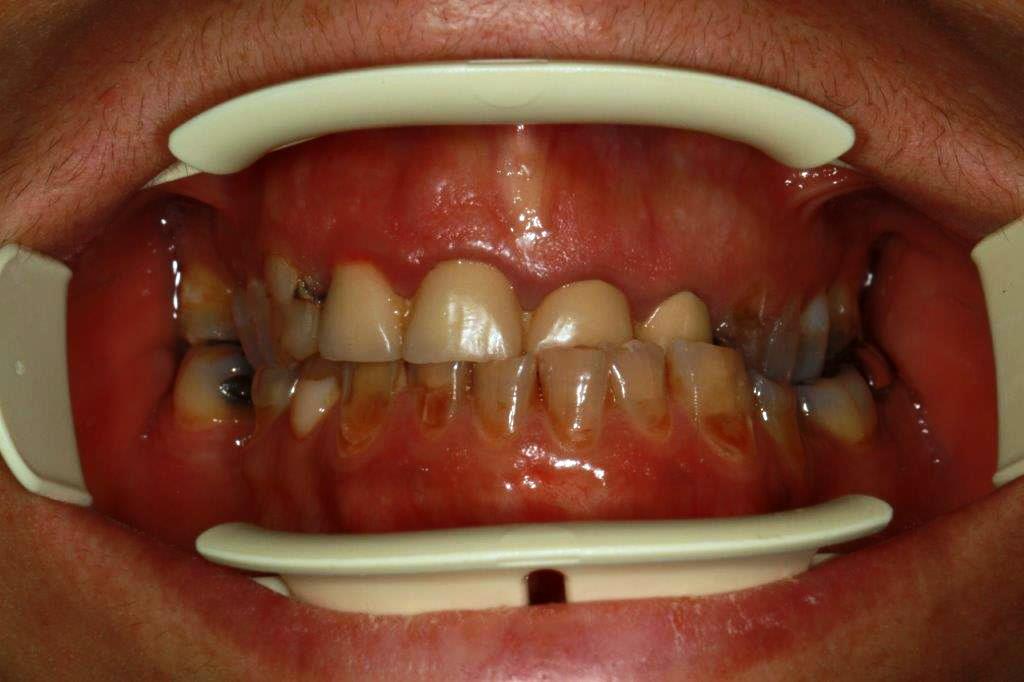

patiente 48 ans ...voudrait pouvoir manger et sourire...

Chouette cas, le plus dur sera évidemment de lever l'articulé croisé.

La DV est-elle conservée? Ce sera plus simple si il faut la remonter.

Non je ne croyais pas que ce cas se ferait, et la patiente vient de decider...donc empreintes et réflexions.

Devis accepté acompte versé il me reste a trouver la solution.

À priori travail sur dents vivantes sauf celles qui sont. Déjà traitées dv légèrement modifiée,et retablir une occlusion standard...un peu chaud quand même.

Pas d'implant prévu ni ortho

On va faire chauffer l'Emax....